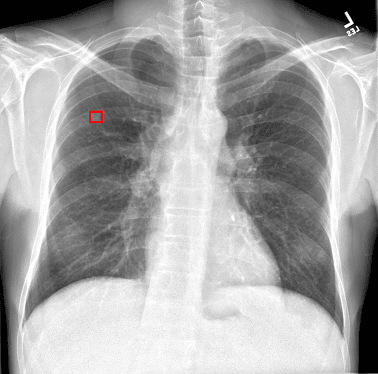

迷いを与えず、邪魔をしない表示方法

EIRLが検出した箇所を、明確に矩形で表示します。これにより、原画像の情報を損うことなく、直感的に検出箇所を確認できます。